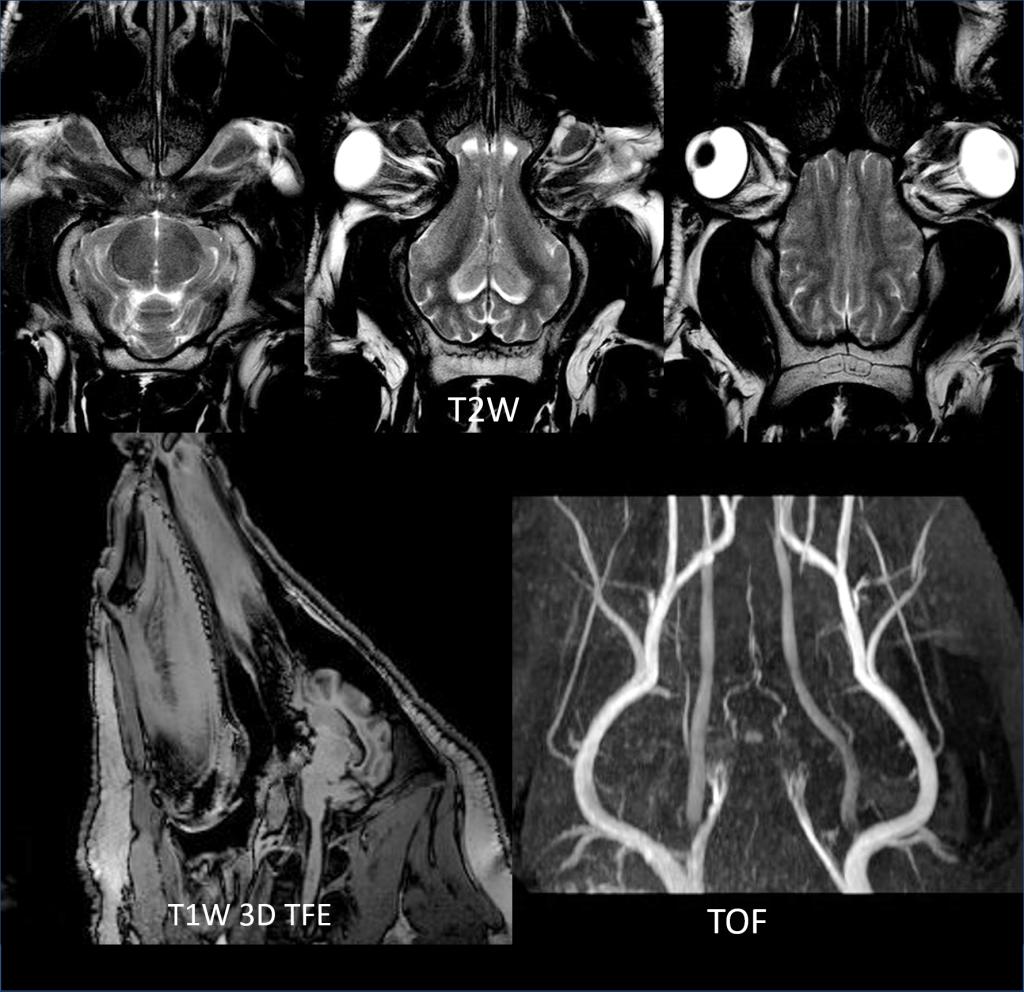

中心的研究团队包括多名医学影像领域的著名科学家和青年骨干,以医学成像和临床应用研究为核心,推动其在中国的发展,并在科技创新、产业结合方面提供多学科全球化的科研、教学和临床服务。影像中心拥有两台先进的3T全身磁共振成像系统(Philips Ingenia CX 3.0T和Siemens Prisma 3.0T),一台超高场5T全身磁共振成像系统(联影 Jupiter 5.0T),多套超声成像系统(含一台ICONEUS 脑功能超声成像系统),以及配套的成像技术、软硬件开发平台、图像数据处理工具和临床图像处理软件。中心的专业运行和技术支持团队以磁共振平台为核心,面向用户提供优秀的基础科学研究、成像技术研发和临床医学转化服务。

影像中心自成立以来,承担了科技部、国家自然科学基金委、卫生部、北京市科委等近百项国家和省部级项目,收到各种研究经费支持达5000万余元,已发表论文600余篇,发明专利60余项,国际专利10余项,培养学生130余人,获得各种奖励30余项。影像中心已成为全球重要的医学影像尤其是磁共振技术研发中心,开发出大视野高分辨血管壁多对比度成像、三维心肌定量成像、定量血流成像、定量生理成像、无变形高分辨率弥散成像等诸多原创技术,同时这些技术被广泛地应用在多项大规模临床人群队列研究当中形成了针对心脑血管、神经变性性疾病等原创性影像学解决方案。